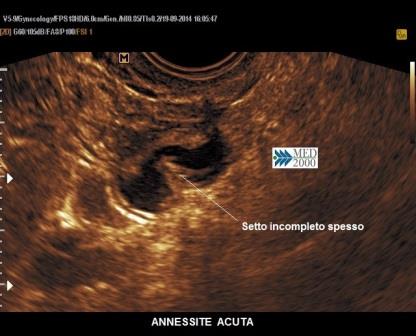

Il segno ecografico caratteristico delle fasi iniziali è la presenza di una tumefazione annessiale adiacente all'ovaio, isoecogena col miometrio, di forma tubulare o ovoidale, non sempre facilmente distinguibile dall'intestino; un operatore esperto può coglierne i segni distintivi: assenza di peristalsi, dolore evocato dalla pressione mirata con la sonda endocavitaria (pain mapping), presenza di una discreta o ricca vascolarizzazione al color/power Doppler. Successivamente, con la formazione di una piosalpinge, la tuba si distende assumendo una morfologia tubuliforme per la presenza di liquido ad aspetto ipoecogeno, disomogeneo, dovuto all'accumulo di pus e sangue e la parete tubarica si ispessisce per l'edema conseguente alla flogosi; alcuni Autori hanno proposto un cut-off di 5 mm. per indicare l'ispessimento della parete tubarica, mentre altri si rifanno all'impressione soggettiva dell'ecografista. In sezione trasversa si osservano delle protrusioni endoluminali iperecogene legate all'edema delle pliche endosalpingee che danno origine ad un segno ecografico caratteristico, il "segno della ruota dentata".

Sempre in sezione trasversa è possibile individuare dei setti incompleti spessi che non raggiungono la parete tubarica opposta. Questo segno non sembra essere caratteristico delle forme acute in quanto è possibile osservarlo anche nelle idrosalpingi.